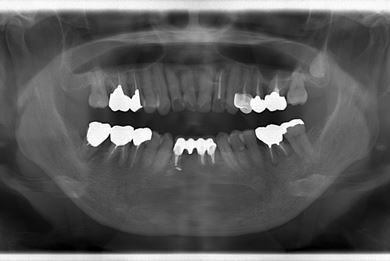

| 性別/年齢 | 女性 / 55歳 | ||||||||||||||||||||||||||||||||

| 主訴 | 20年程前に矯正のため義歯にしたものの具合が悪いので、いいものにかえて欲しい。歯ぐきから骨が見えてきたところがあるので、治療して欲しい。 | ||||||||||||||||||||||||||||||||

| 治療方針 | 保存不能な歯を抜歯し、セラミック治療にて、機能的・審美的回復を行う。 | ||||||||||||||||||||||||||||||||

| 治療内容 | ジルコニアオールセラミッククラウン4本(オールセラミック用土台3本) | ||||||||||||||||||||||||||||||||